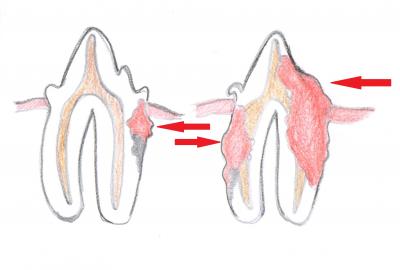

Příčina vzniku resorpčních lézí není zcela objasněná. Uvádí se, že se na vzniku může podílet onemocnění dásní, bakteriální a virové infekce, anatomické uspořádání zubů i složení krmiva. Na obrázku můžeme vidět, jak léze postupuje. Vytvoří se dutinka, která se šíří směrem ke dřeni (do centra zubu). Na povrchu je dutinka pokryta granulační tkání. V konečném stádiu se může odlomit celá korunka a v dásni zůstanou pouze kořeny zubu.